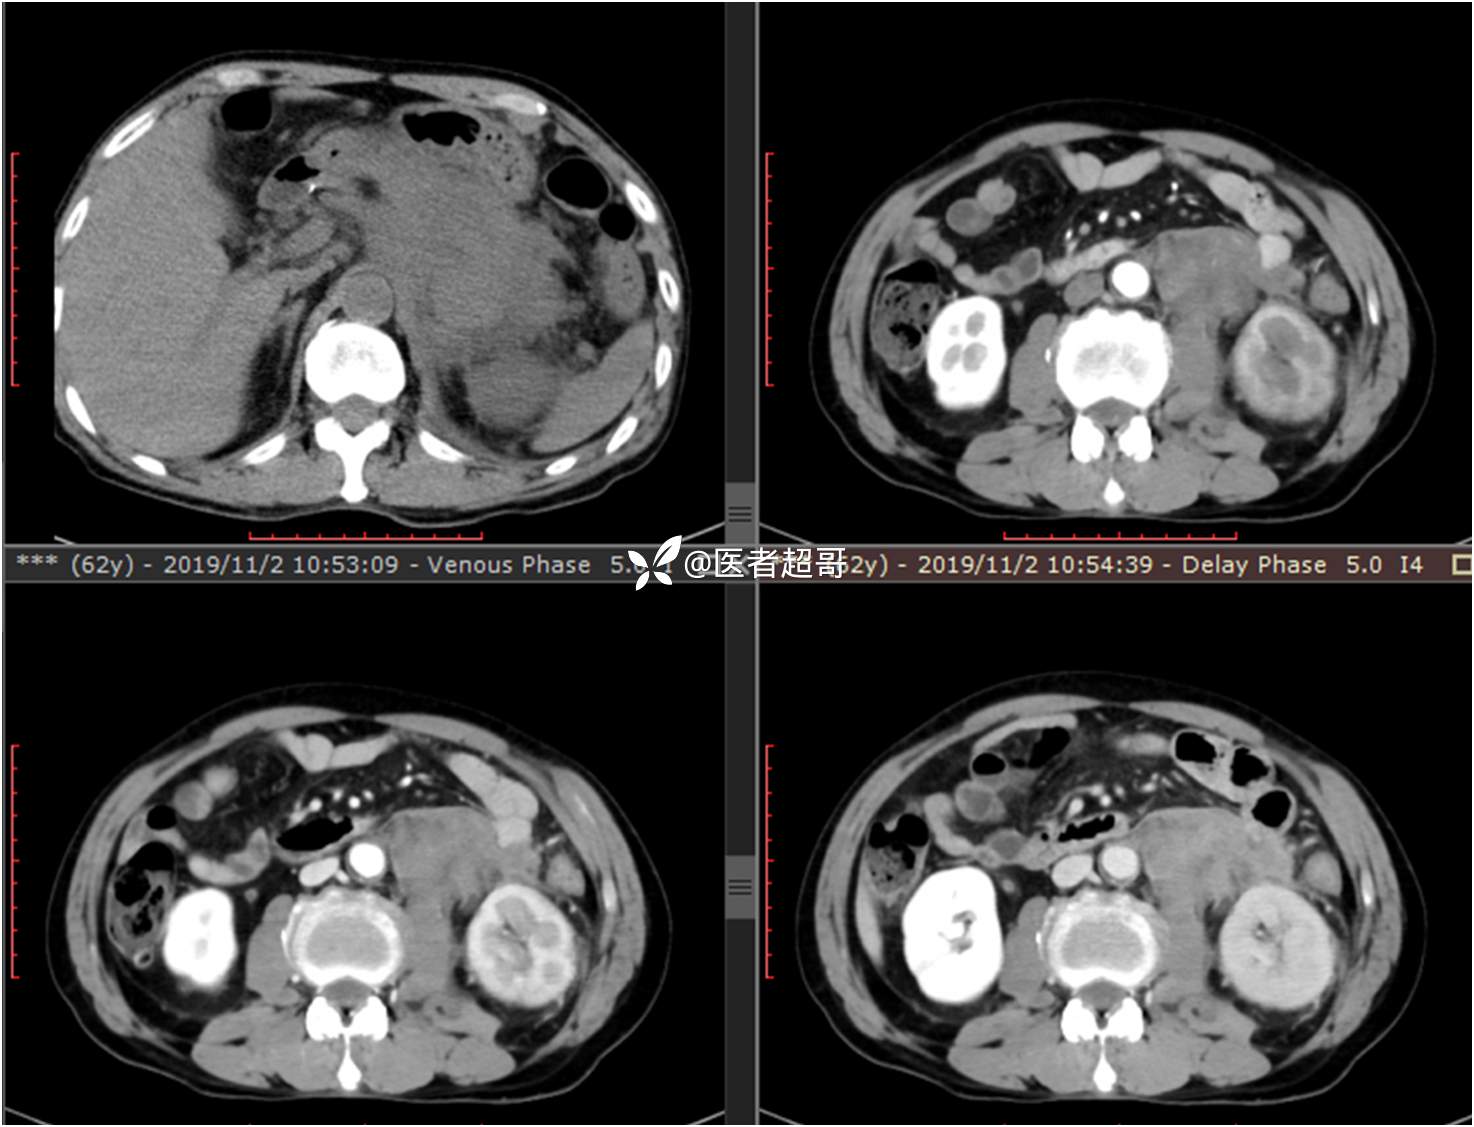

现病史:患者于1月前无明显原因及诱因出现左上腹部疼痛,为间断性疼痛,无恶心、呕吐,无寒战、高热,无腹胀、腹泻等伴随症状,在外未行特殊处理,患者于1周前自觉疼痛加重,为求诊治患者曾就诊于市东城医院,行全腹部强化CT提示:左肾上腺区肿块,符合恶性肿瘤侵犯左肾、胰腺及腹膜后大血管CT表现,行保守治疗,症状缓解,今患者为求进一步诊治,来我院就诊,行腹膜后占位穿刺活检病理提示:(腹膜后占位穿刺)小细胞背景内见细胞浆红染的神经节样细胞,建议到病理科加做免疫组化进一步明确诊断,遂以“腹膜后肿物”收入院,患者自发病以来,神志清,精神可,饮食、睡眠差,大小便正常,体重未见明显改变。